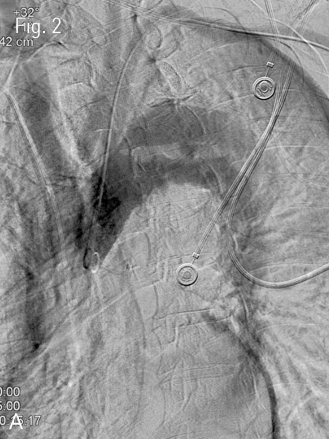

Fig 2A

Fenestration was performed to restore renal artery flow via left brachial and right femoral accesses. (A) Thoracic aortogram via brachial access demonstrated the intimal flap, tear site and both true lumen and false lumen of the dissection.

Fig 2B

(B) 5-Fr RDC guiding catheter and guidewire were successfully advance into the false lumen with careful manipulation.

Fig 2C

(C) Angiogram of the false lumen was obtained to evaluate the extent of dissection and relationship of the intimal flap.

Fig 2D

(D) Angiogram of the true lumen via femoral access showed the luminal narrowing of true lumen at infrarenal level and mesenteric arteries were arising from true lumen.

Fig 2H

(H) After puncture, serial balloon dilatation was performed upto 25mm in diameter.